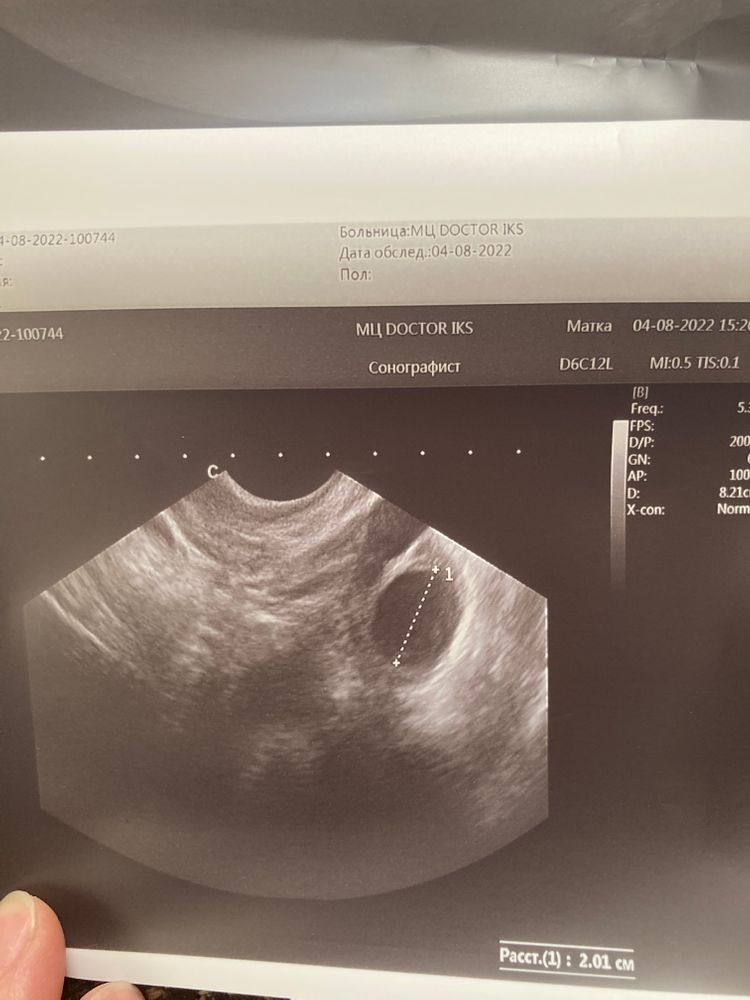

Точно киста ?или дф?жт?

19мм это же получается да😅да вроде доминантый фолликул еще

Фолликулярная киста 14дц что делать дальше? Все таки не киста фолликулярная??